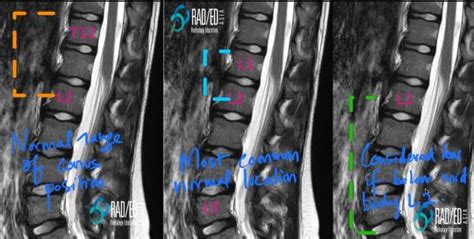

Now, why is the L1 vertebral level so special when we talk about the conus medullaris? Well, as I just mentioned, it’s the most common endpoint for the conus medullaris in adults. This anatomical standard is incredibly useful. For medical professionals, knowing this typical termination point helps them interpret imaging studies like MRIs and CT scans. If they see the conus medullaris extending much lower, say down to L3 or L4, it could indicate a developmental abnormality or a condition like a tethered spinal cord , where the spinal cord is abnormally attached to surrounding tissues, restricting its movement. This restriction can lead to progressive neurological damage. Conversely, if the conus medullaris ends higher up than usual, it might also signal an issue. The L1 level serves as a crucial reference point for spinal surgeries, injections (like epidurals or spinal taps), and the diagnosis of various neurological conditions. For example, injuries to the spinal cord at or above the L1 level can result in paralysis of the legs, while injuries below might spare leg function but affect bowel and bladder control. The cauda equina, originating from the end of the conus medullaris, is more resilient to direct trauma than the spinal cord itself because it’s a collection of individual nerve roots that can potentially regenerate to some extent. However, significant compression or damage to the cauda equina can still lead to permanent deficits. So, you see, the L1 vertebral level isn’t just some random number; it’s a vital landmark that helps us understand the functional anatomy of the lower spine and diagnose potential problems. It’s like a signpost in the complex landscape of our nervous system, guiding medical professionals toward accurate diagnoses and effective treatments. The variability in the exact termination of the conus medullaris, even within the L1-L2 range, is also a factor considered in clinical practice, highlighting the importance of individualized assessment.